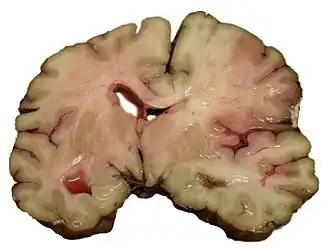

Ишемический инсульт в бассейне средней мозговой артерии. Аутопсия.

Фиолетовым обозначена зона инфаркта. Стрелкой показана дислокация срединных структур головного мозга

Ишемический инфаркт является самым частым проявлением (75 % случаев) ишемического инсульта. Он выглядит как очаг серого размягчения ткани мозга. При микроскопическом исследовании среди некротизированных масс находят погибшие нейроны[28]:360.

Геморрагический инфаркт мозга внешне похож на очаг геморрагического инсульта, однако имеет другой механизм возникновения. Первично возникает ишемия головного мозга; вторично — кровоизлияние в ишемизированную ткань. Геморрагический инфаркт чаще встречается в коре мозга, реже — в подкорковых узлах[28]:360.